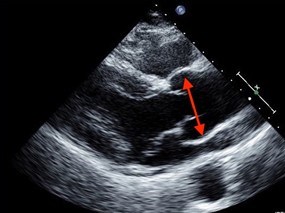

Imaging findings of Marfan syndrome: What radiologists need to know

In a recent article for Aunt Minnie, Sanjeev Bhalla, MD, and Mensur Koso, MD, both from the…

Dr. Alan Braverman Discusses Important Role Radiologists Play in Early Marfan Diagnosis

Dr. Alan Braverman, director of the Marfan Syndrome and Aortopathy Center at the Washington…